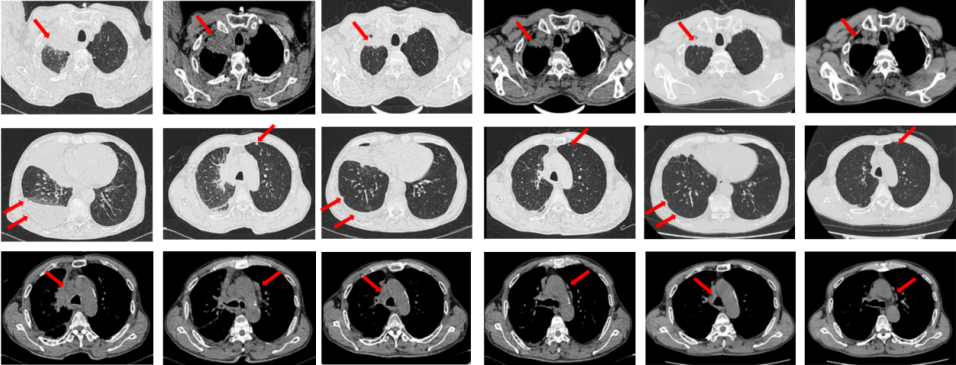

2023年9月复查评效PD。成功入组“一项开放、多中心对比谷美替尼与多西他赛在既往接受免疫治疗和含铂双药化疗后进展的驱动基因阴性且伴有MET扩增的局部晚期或转移性非小细胞肺癌患者中的随机对照III期临床研究”。成功随机到试验组,口服谷美替尼至2024年10月,期间复查最佳评效PR。

图3:A.二线治疗后病情进展,右肺上叶新发肿物较前明显增大,新发无症状脑转移病灶;B.经谷美替尼(300mg po qd)治疗3个月后复查肺内病灶及颅内病灶较前明显缓解

67岁女性患者,无既往病史。2019年10月患者因右侧季肋部不适行肺CT提示右肺中叶改变,双肺结节,右侧胸腔积液。行右侧胸腔穿刺引流,送检胸腔积液,液基薄层结果提示肺腺癌。确诊为右肺中叶恶性肿瘤cT2bN1M1a IVA期。基因检测(胸腔积液):EGFR L858R突变。建议患者口服奥希替尼,患者拒绝。2019年11月始口服埃克替尼,定期复查,最佳评效PR(图5)。

图5:A.第2例患者的基线影像资料,由上至下依次为右肺肿物、双肺转移灶及右侧胸腔积液;B.EGFR-TKI一线治疗后最佳复查评效,肺内病灶较前缩小,胸腔积液较前明显吸收。

2020年11月复查评效PD。复测基因检测(血检):T790M阳性,改行奥希替尼治疗,期间评效均为SD(图6)。

图6:A.埃克替尼靶向治疗后病情进展,肺内病灶较前增大,右肺近胸膜处新发转移灶;B.更换三代EGFR-TKI治疗后复查多处病灶未见明显变化。

如图7所示,2021年7月复查评效PD。重新行右肺穿刺取得病理,提示腺癌。NGS组织基因检测:MET基因扩增(变异倍数)4.0倍。改行赛沃替尼联合奥希替尼治疗。治疗10日后突发一过性寒战伴低血压,不除外药物相关,对症治疗后好转。复查评效达PR,因患者无法耐受药物不良反应,改行奥希替尼联合克唑替尼治疗至今,定期复查,最佳评效PR,末次评效SD(2024年7月)。

图7:A.奥希替尼治疗后病情进展,右肺内病灶较前再次增大,同时右肺内新发转移灶;B.出现MET扩增后,奥希替尼联合MET-TKI治疗后肺内病灶较前明显缩小;C.当前方案治疗持续有效。